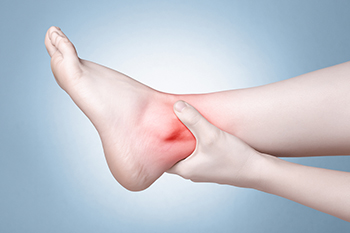

Ankle pain while walking can be caused by several conditions, including gout, osteoarthritis, and peripheral neuropathy. Gout is a form of inflammatory arthritis caused by a buildup of uric acid crystals in the joint, leading to sudden, intense pain, swelling, and redness. Osteoarthritis results from the gradual wear and tear of cartilage, causing stiffness, aching, and decreased mobility in the ankle joint. Peripheral neuropathy involves nerve damage, often due to diabetes or other medical conditions, and can cause burning, tingling, or numbness in the ankle and foot. The pain may feel sharp, throbbing, or burning and can worsen with activity. A podiatrist can provide an accurate diagnosis through a physical examination, medical history review, and imaging or nerve studies. Treatment options may include medication, lifestyle modifications, orthotics, o,r in some cases, surgery. To address ankle pain effectively and improve mobility, it is suggested that you schedule an appointment with a podiatrist.

Ankle pain can have many different causes and the pain may potentially be serious. If you have ankle pain, consult with Mark Isenberg, DPM from Center for Podiatric Excellence. Our doctor will assess your condition and provide you with quality foot and ankle treatment.

Ankle pain is any condition that causes pain in the ankle. Due to the fact that the ankle consists of tendons, muscles, bones, and ligaments, ankle pain can come from a number of different conditions.

Symptoms of ankle injury vary based upon the condition. Pain may include general pain and discomfort, swelling, aching, redness, bruising, burning or stabbing sensations, and/or loss of sensation.

Due to the wide variety of potential causes of ankle pain, podiatrists will utilize a number of different methods to properly diagnose ankle pain. This can include asking for personal and family medical histories and of any recent injuries. Further diagnosis may include sensation tests, a physical examination, and potentially x-rays or other imaging tests.

Just as the range of causes varies widely, so do treatments. Some more common treatments are rest, ice packs, keeping pressure off the foot, orthotics and braces, medication for inflammation and pain, and surgery.